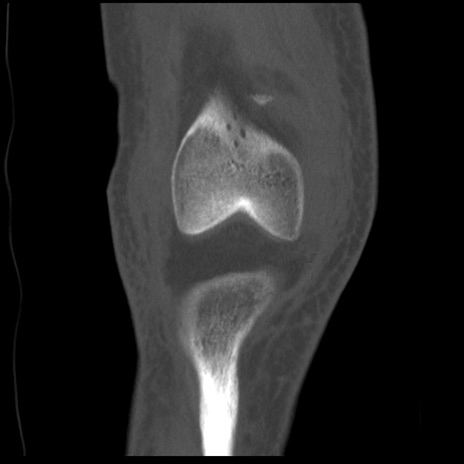

右膝関節CT

矢状断像